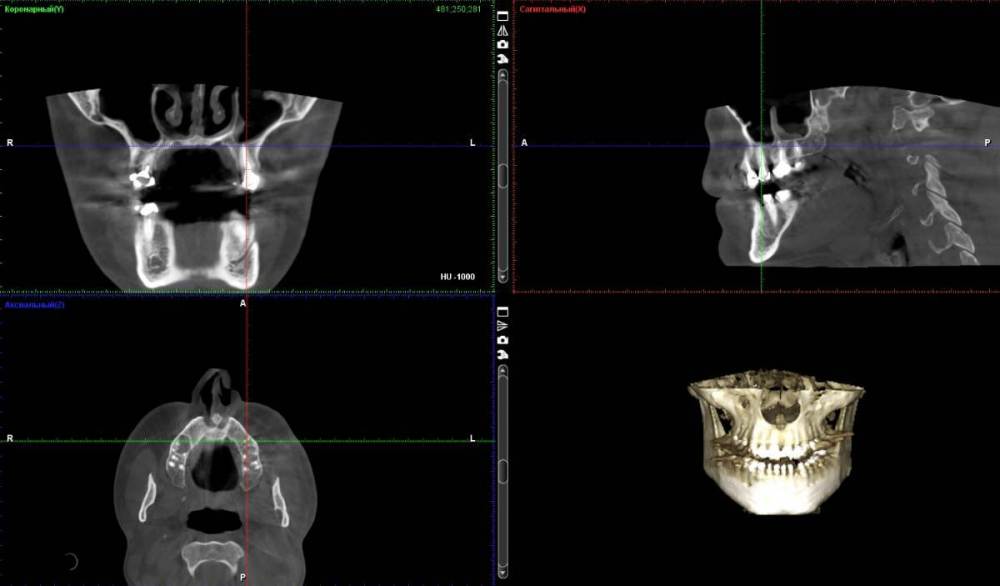

neumann Опубликовано 24 марта, 2022 Автор Поделиться Опубликовано 24 марта, 2022 @Женька спасибо за ответ. вот такие срезы? Ссылка на комментарий

Женька Опубликовано 24 марта, 2022 Поделиться Опубликовано 24 марта, 2022 @neumann уже что-то теперь нужны срезы именно "вокруг" этого зуба На первый взгляд это просто анатомическое образование. Так называемая септа (перегородка) в верхнечелюстной пазухе. И повода для беспокойства нет (если судить именно по тем срезам что Вы предоставили. Ссылка на комментарий